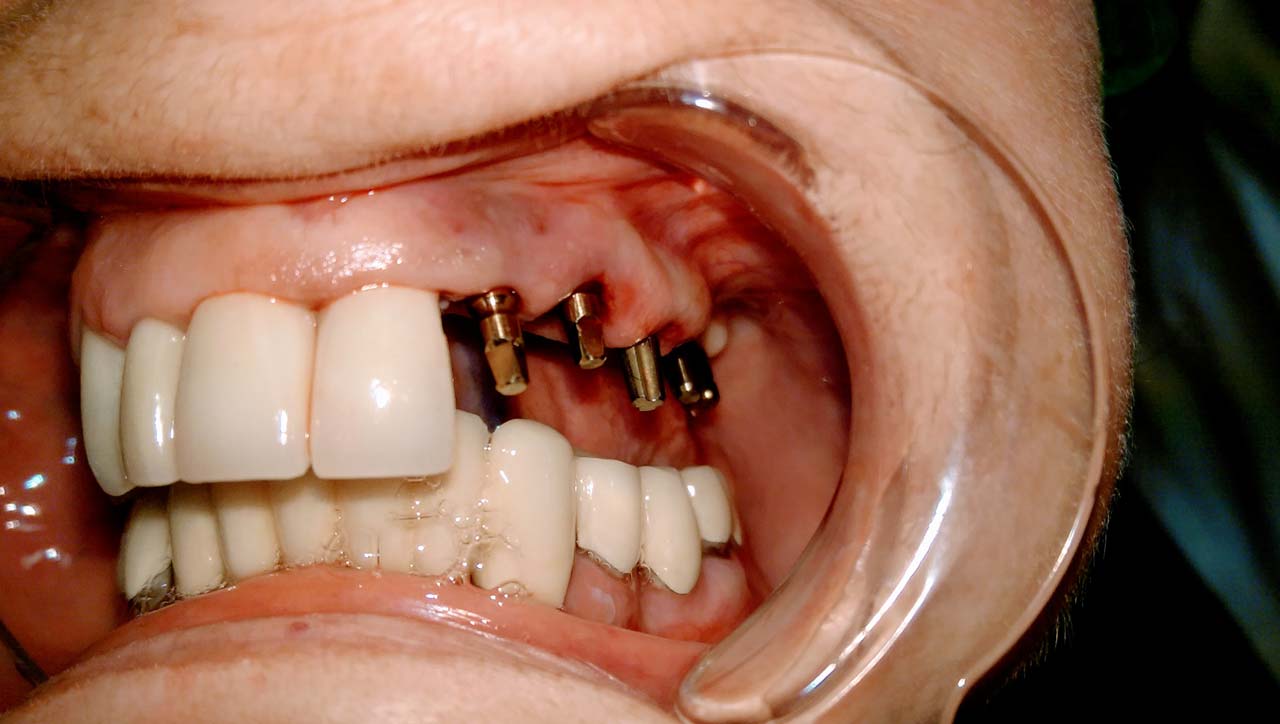

Alsó állcsont teljes rehabilitációja 72 óra alatt

Alsó állcsont teljes rehabilitációja 72 óra alatt, azonnal terhelhető implantátumokkal súlyos paradontitisben szenvedő dohányzó páciens esetében. Az alsó állcsont fogai mind mozogtak az előrehaladott fogágypusztulás miatt.

A fogakat eltávolítottuk, a gyulladt, fertőzött csontot kitakarítottuk, kifertőtlenítettük, majd azonnal implantáltunk.

Svájci, IHDE márkájú, azonnal terhelhető implantátumokat helyzetünk be, és ezekre harmadnapra rögzített, hosszútávú, fémvázas, esztétikus műanyaggal leplezett hidat ragasztottunk be.

Ezt az ideiglenes hidat a sebek gyógyulása miatt használjuk, de tartóssága miatt véglegesként is használható. A legtöbb esetben, ahogy itt is, 6 hónap múlva porcelán hídra cseréljük, a teljes gyógyulás után.